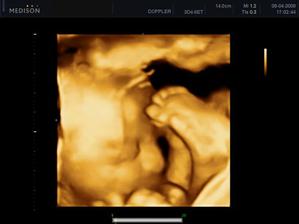

- 5.1.2009 screening dopadl dobře a viděla jsem mimíse jak krásně hýbal ručičkama

- další kontrola a tripple testy (17+3). UTZ v pořádku, výsledky krve budou při další kontrole. a konečně máme potvrzeno pohlaví - JE TO KLUK!!!! dokonce jsem dostala i fotku pindíka tak jí ukazuju všem v okolí 🙂). objednala jsem se k zubaři, na EKG a internu. velký UTZ + další kontrola 3.3.

- 3.3. kontrola v pořádku, byla jsem na 1. velkém UTZ - tam je také vše v pořádku a mimís roste jak má